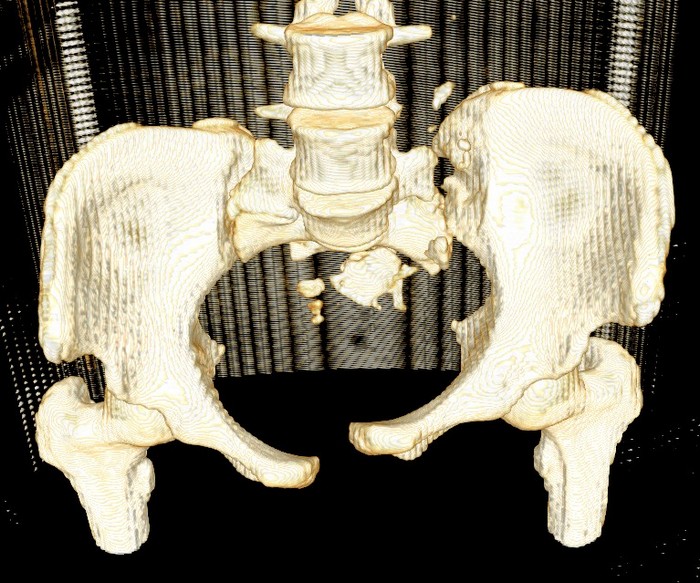

Девочка 14 лет. Кататравма (падение с высоты 4-5 этажа). Вертикально нестабильный перелом таза со смещением, разрывом лонного и левого подвздошно-крестцового сочленения, перелом крестца, открытый перелом костей голени. Ребёнок оперирован на 10-е сутки после травмы - выполнили максимально возможную репозицию на ортопедическом столе, синтез лонного сочленения реконструктивной пластиной (из имеющихся пластин - на 7 дыр - самая длинная, получилось только по 2 шурупа с каждой стороны, поэтому пришлось подстраховаться проволокой), АВФ. Задний комплекс не фиксировали ввиду отсутствия канюлированных (да и неканюлированных)шурупов должной длинны.В настоящий момент перед нами стоит вопросов:1. Обязательно ли фиксировать подвздошно-крестцовое сочленение, либо фиксации АВФ будет достаточно? Аппарат стоит достаточно стабильно, девочка при перемещениях в пределах постельного режима болевых ощущений не испытывает.2. Что делать с отломком крестца, который довольно значительно смещён кпереди? В настоящий момент никаких проблем с дефекацией у больной нет, хотя, глядя на КТ, создаётся впечатление, что отломок прямо-таки лежит на прямой кишке. Репонировать-фиксировать? Просто удалить? Вообще не трогать? Не создаст ли он в дальнейшем проблем во время родов?Хотелось бы знать мнение уважаемых коллег.Заранее спасибо.

Здравствуйте, Сергей! Нестабильный перелом типа С подлежит обязательной задней фиксации или илиосакральными винтами, или пластиной, или стяжкой (кто что лучше умеет и чем оснащен). Возможен циркулярный АВФ (Уральский НИИТО). В Вашем случае, при невозможности восстановления заднего комплекса,- постельный режим до 2-х месяцев. Учитывая недостаточную репозицию в крестцово-подвздошном сочленении в будущем девочка обречена на хронический болевой синдром. Может быть стоило выполнить репозицию отломков в аппарате, а вторым этапом делать погружной остеосинтез. Костный фрагмент, думаю, можно оставить. После такой травмы речь будет идти о кесаревом сечении, а не о родах естественным путем.

Это не частый случай в детской практике. Вы очень хорошо сопоставили и фиксировали переднее полукольцо. Крестцово-подвздошное осталось в приличном смещении. Прекрасно - что нет неврологической клиники. Сейчас больная лежит. Поэтому всё хорошо. Учитывая соотношение крестец-подвздошная кость - кажется, что первые же проблемы возникнут при попытке поставить больного на ноги. Разорваны важнейшие стабилизирующие и воспринимающие нагрузку связки в системе позвоночник-крестец-таз. В таком положении фрагменов их адекватное восстановление и последующее функционирование , как мне кажется, не возможно. В возрасте 14 лет это взаимоотношение критично. Я имею в виду отсутствие репозиции. появление нестабильности, по-видимому, будет неизбежно. Это моё маленькое скромное мнение. Всё же надо было начинать сзади. Именно с репозиции. Фиксацию, ИМХО, можно было бы на безрыбье временно сделать и спицами (например-с резьбой) интраоперационно. В идеале - с навигатором, чтобы не задеть крестцовый канал, или с пальцем, контролирующим положение отломков над гребнем подвздоной кости и "навигирующим" проведение спицы. Сейчас Вам это сделать помешает LCP, жёстко фиксирующая переднее полукольцо и смещенное положение отломков. АВФ не "прижмёт" подвздошную кость к крестцу, и не выполнит репозицию. Возраст больной, мне кажется, не простит в дальнейшем погрешность в положении костей и, чем дальше, тем труднее будет исправлять . Это только мнение и ничего личного.Прямая кишка здесь в меньшей степени заинтересована - это вовсем не главное. Вероятные роды в насоящей тактике лечения совсем не играют решающей роли. Всё же - как неврология?